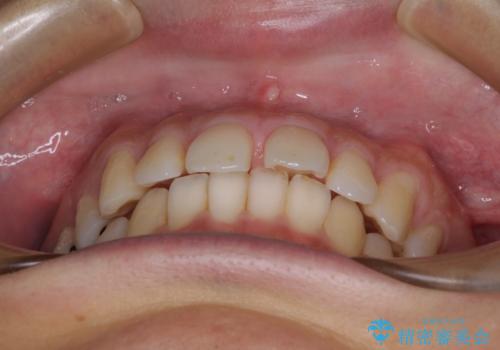

深い咬み合わせと前歯の隙間 ハーフリンガルによる矯正治療

- 咬み合わせにより上顎正中に隙間ができているとのことで来院された患者様です。